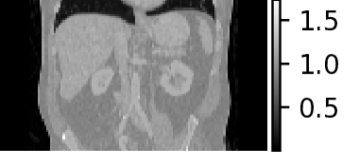

| Density map (g/cc) | Organ dose map (mGy) | |

Axial |

![]() |

|

Sagittal |

Coronal |

For individualized patient organ dose, patient CT images were used to generate patient-specific voxelized phantoms that contain spatial maps of both material type and mass density. The CT images were first resampled to isotropic voxels of mm3 to keep the computational demands reasonable. The density mapping was performed following a piece-wise linear curve which defines the densities of the mixture of water and bone [45]. Figure 5 visualizes the MC-GPU inputs of mass density and corresponding material map in different views (axial, sagittal, coronal) of a patient CT scan.

We simulated a helical scan from the most superior to most inferior slice for the geometry of a GE Revolution CT scanner. Table 1 lists the modified set of parameters for our MC-GPU configuration. We repeated the MC-GPU dose simulation with uniformly spaced apart start angles . Considering the actual start angles cannot be controlled prospectively, therefore, we averaged the dose maps to obtain the dose map [41].

where, is the voxelized phantom and denotes the set of all the parameters used to configure the MC-GPU simulation. MC-GPU dose is reported as eV/g/photon and was scaled to the more standard mGy for a 100 mAs scan with constant tube current, using a scanner-specific calibration to convert a simulated 32 cm CT dose index (CTDI) phantom to a physical CTDI measurement (1 eV/g/photon = 1.8143 mGy/100 mAs). Figure 5 visualizes a representative dose map. Using a threshold g/cc in the voxelized phantom, we masked out the air and obtained the patient body dose map. Therefore, from average dose map in (2), the final dose map is obtained as

An example patient CT density map and the corresponding organ dosemap (segmented organ contours overlaid on the dosemap) at three different views obtained from the modified MC-GPU tool can be seen in Figure 5. Moreover, Figure 6 shows the distributions of organ and patient body doses for all the patient CT scans.